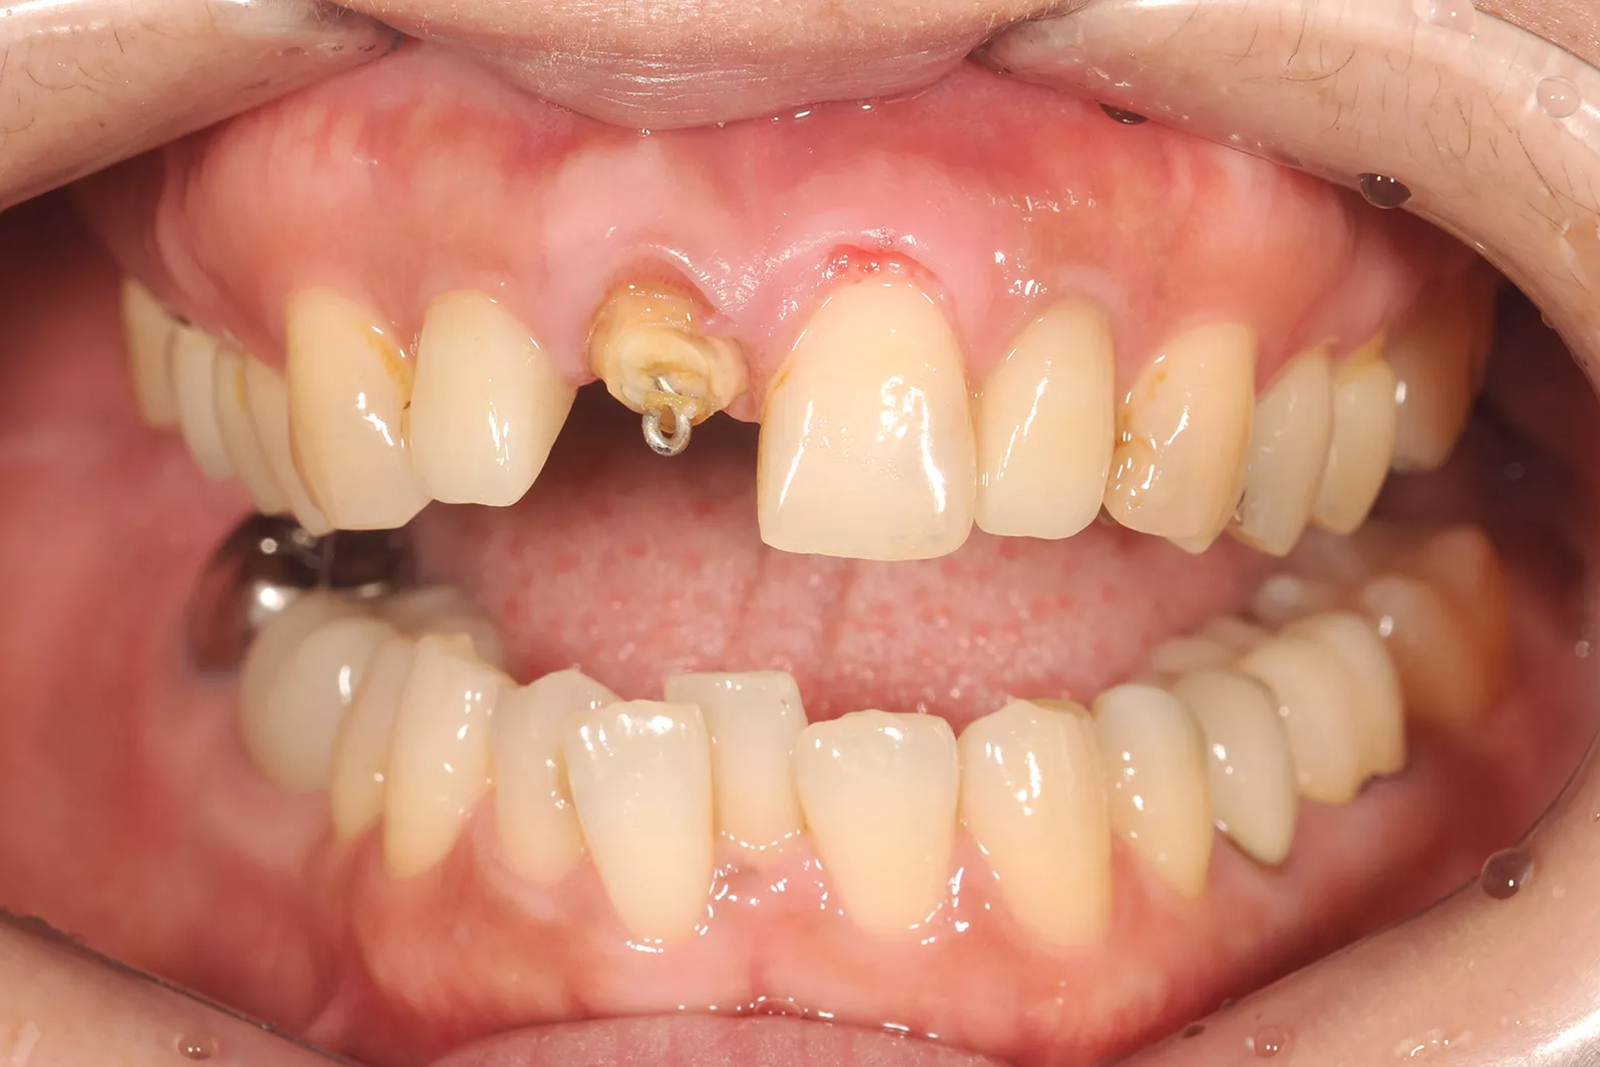

重度の虫歯も抜歯を回避「エクストルージョン法」

虫歯が進行して歯の頭が崩れてしまうと、被せ物を支える土台がなくなり、多くの歯科医院では抜歯を提案されることがあります。

しかし当院では、歯の根を少しずつ引き上げて健全な部分を露出させる「エクストルージョン法」により、歯を残せる可能性があります。